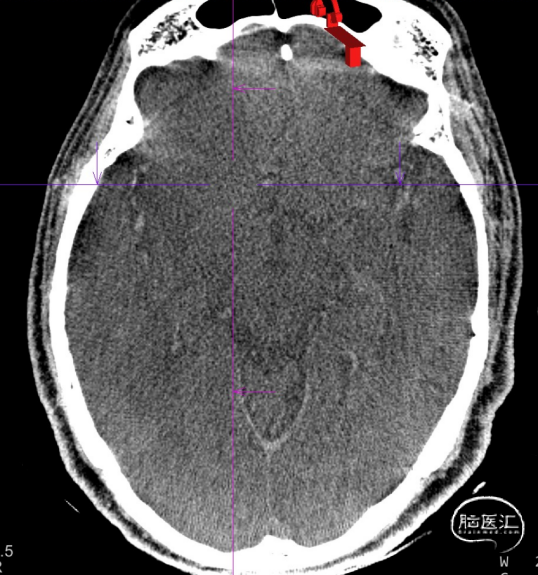

患者为急性脑梗死,头颅CT未见明显低密度病灶,CTA提示:右侧颈内动脉及右侧大脑中动脉M1段闭塞,远端分支减少,显影浅淡。目前患者神经功能缺损严重,有急诊取栓手术指征。

术后第一天复查颅脑CT未见异常染色及大面低密度病灶。

查头颅MRI:右侧基底节区、右侧顶颞岛叶急性脑梗死。